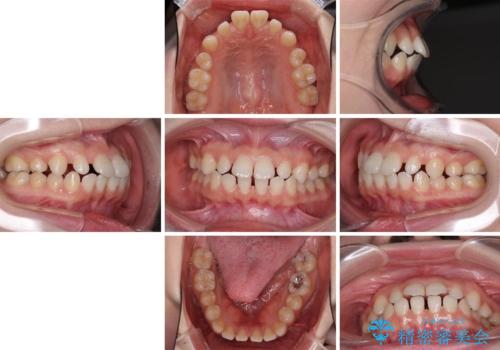

- 歯の欠損による隙間だらけの歯並びを気にして来院された患者様です。

上顎左右1本ずつ欠損していたため、歯列矯正により欠損部位にスペースを集め、その後欠損部位をインプラントにて補綴することとしました。

インビザラインによる矯正治療も提案しましたが、長時間の装着や自己管理が難しいとお考えで、ワイヤーによる矯正治療を行いました。

歯並びは比較的早めに整いましたが、インプラントを埋入するにあたって前後の歯根位置を改善する必要があり、矯正治療に期間を要することとなりました。